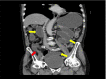

Pericecal fossa strangulated internal hernia

Pericecal fossa internal hernias are a rare cause of intestinal obstruction, and high clinical suspicion is required to diagnose them.